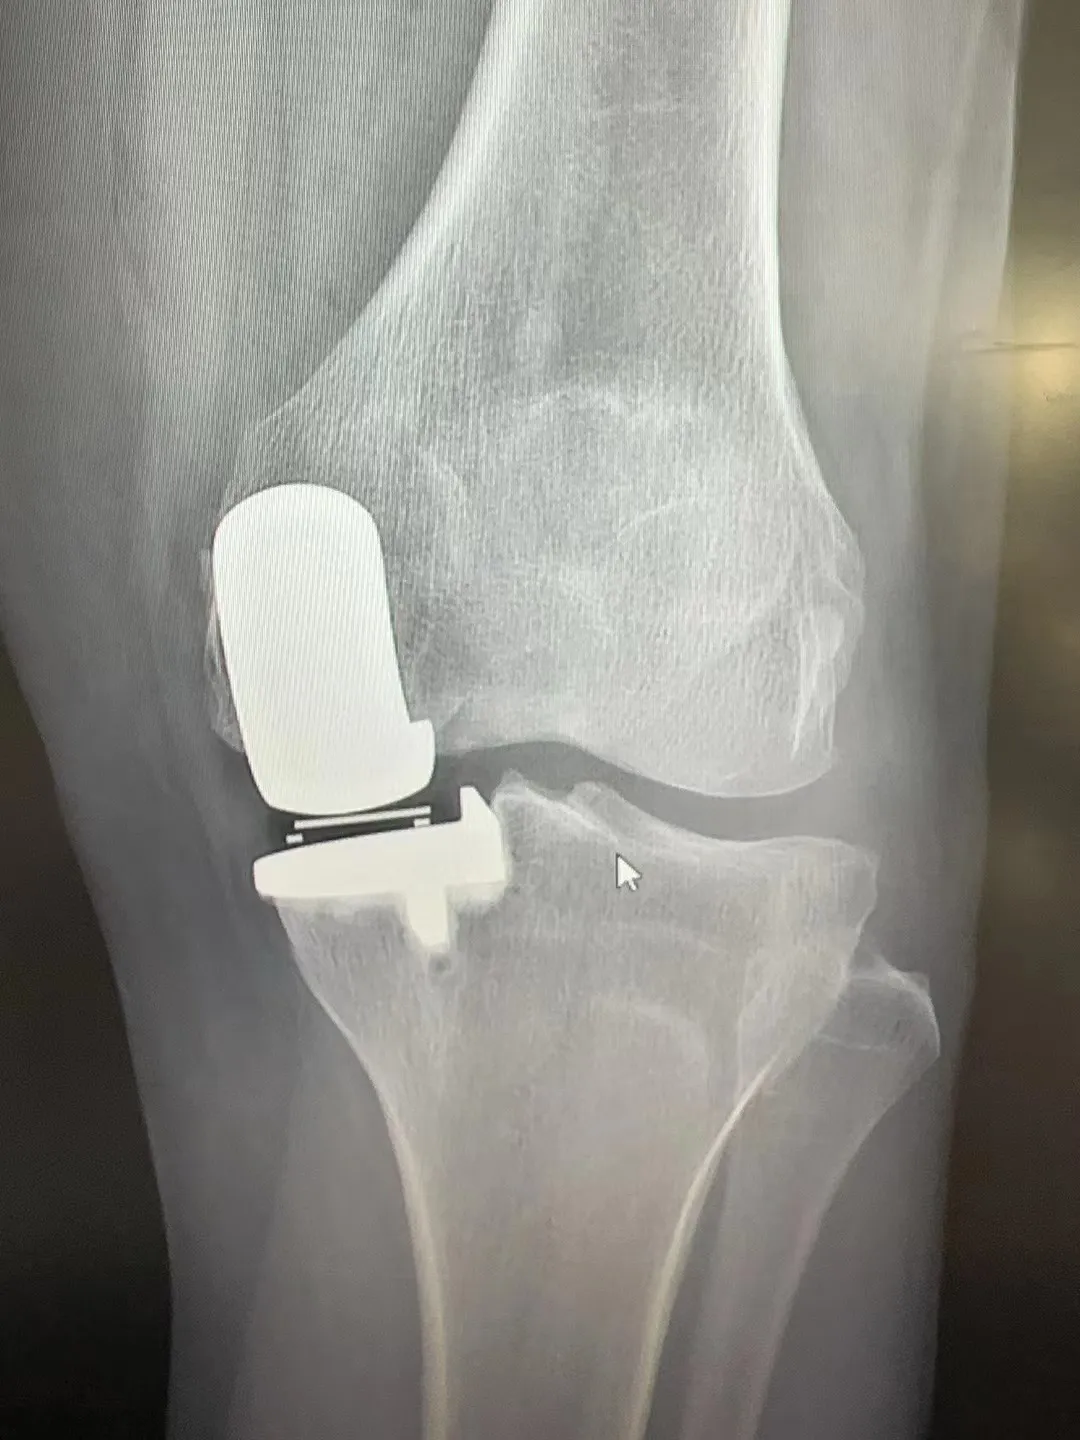

术后患者膝关节情况